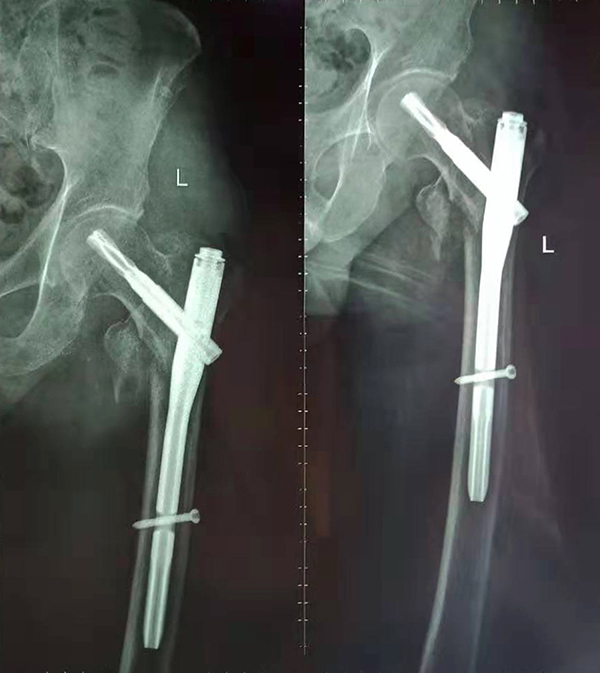

經(jīng)術(shù)前仔細(xì)的檢查和評估,與張爺爺家屬充分溝通,決定了實(shí)施閉合復(fù)位PFNA內(nèi)固定術(shù)的方案,劉鴻程主任說到,該術(shù)式的創(chuàng)傷小、出血少,適合骨質(zhì)疏松病人,術(shù)后解除患者疼痛,可以早期開始活動,便于護(hù)理。

手術(shù)后

9月10日上午,骨科順利完成張爺爺?shù)淖蠊晒谴致¢g骨折髓內(nèi)釘內(nèi)固定術(shù)。手術(shù)過程中麻醉平穩(wěn),術(shù)中出血量少,骨折手術(shù)時(shí)間持續(xù)一個多小時(shí)。